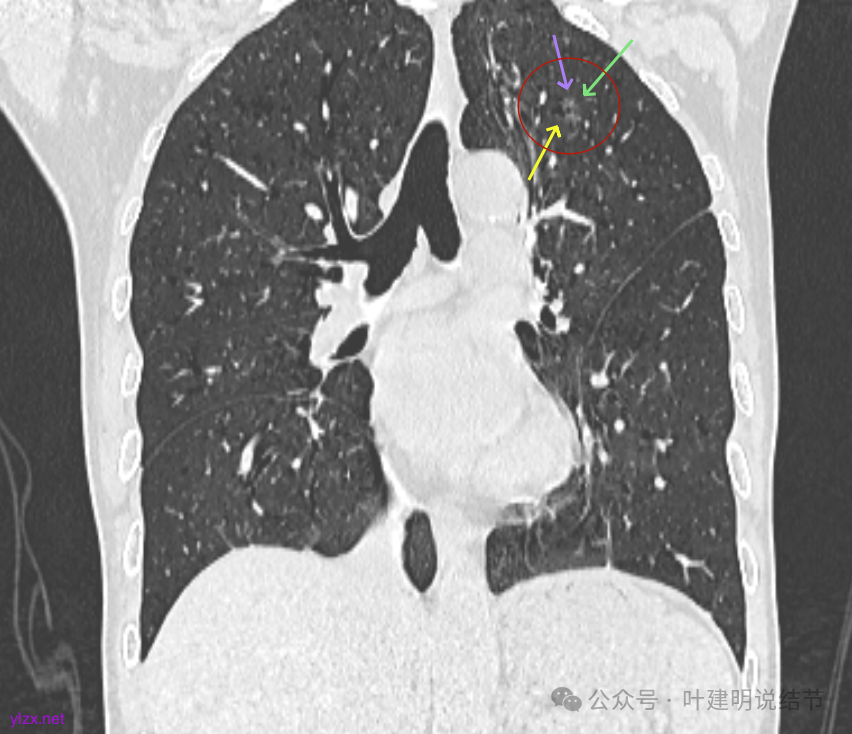

最后看2025年3月的连续层面的影像细节:

左上病灶淡而纯,有微小血管进入。

右上淡磨,轮廓清,空泡明显。

左上的小而局部有细支气管扩张的样子,部分边缘显毛糙,有细毛刺样征。

左上病灶纯磨,轮廓清。

右上淡磨,左下密度较右侧的稍不均一点。

左上病灶冠状位显示纯磨,部分连续细毛刺,灶内有扩张的细支气管似的,整体轮廓清。